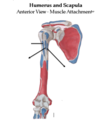

Function of the rotator cuff muscles on the humerus?

Supraspinatus: abductor.

Subscapularus: medial rotator.

Infraspinatus and teres minor: lateral rotators.

Function of the deltoid?

Function of the pectoralis major?

What is the function of the teres major and latissimus dorsi?

Pectoralis major: lateral lip of the bicipital grove.

Intertubericular grove is where the lattisimus dorsi is attaching

The teres major inserts in the medial lip of the bicipital grove. This is why the lat is thought of the lady between two majors.